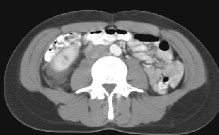

HELICAL CT FINDINGS: The CT was performed on AIC’s multi-slice helical CT (MSCT) scanner. Images with 5 mm collimation were obtained before, immediately following and 5-10 minutes after power injection of IV contrast. The region of the appendix was unremarkable. However, the right kidney and perinephric region were abnormal. Fig. 1 and Fig. 2 illustrate patchy and wedge-shaped low attenuation areas in the right kidney, and Fig. 3 shows stranding/infiltration of perinephric fat around the lower pole consistent with inflammatory changes (arrows).

DIAGNOSIS: The CT images are most compatible with acute pyelonephritis (APN) even without any laboratory results. Shortly after, results of blood work and urinalysis revealed leukocytosis and pyuria substantiating the CT diagnosis.